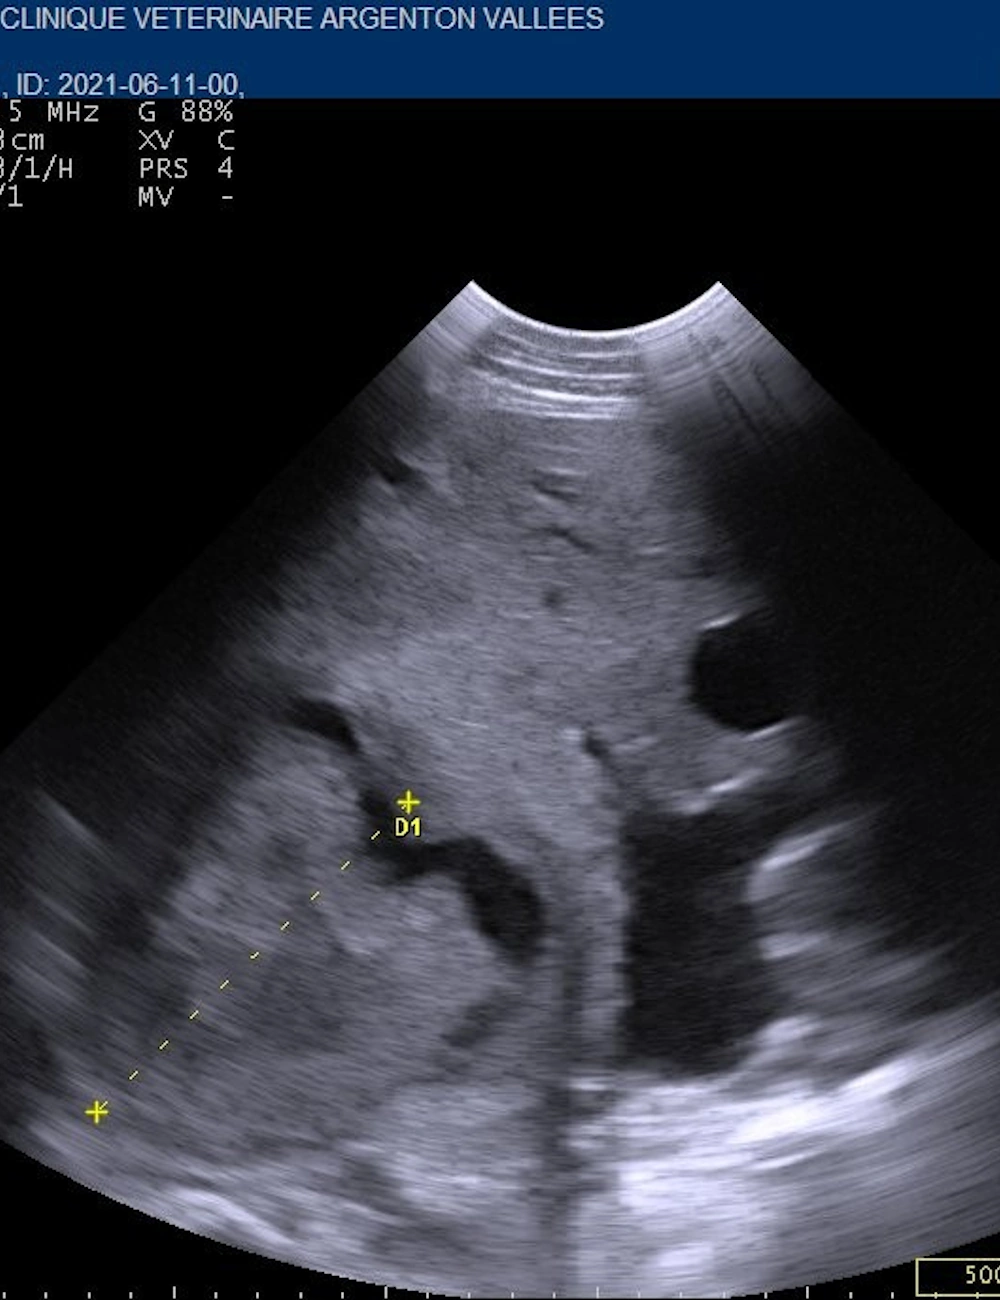

Une échographie digestive bovine

• Médecine interne

• Imagerie